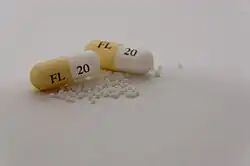

Pharmacological measures

- The treatment of sexual sadism with pharmacological means is not recent, but has been often misconceptualised and requires further trials analysing their effectiveness on larger sample sizes (Foulkes, 2019).

- Nonetheless, some studies (Bradford, 2000) have seen the effectiveness of utilising medication such as anti-androgen and hormonal drugs, as well as the serotonin reuptake inhibitors in the treatment of sexually violent individuals (in accordance with forms of therapy).